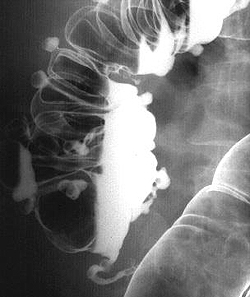

Рентгенографическое исследование толстого кишечника с барием (ирригоскопия) позволяет диагностировать дивертикулит, если невозможно проведение колоноскопии, или она дает неоднозначные результаты. Дивертикулы на рентгенографии определяются в виде образований округлой формы, которые имеют диаметр от 0,5 до 5 см. При дивертикулите на рентгенограмме визуализируются одиночные и множественные выпячивания, а края дивертикулов имеют неровные зазубренные контуры. Если на фоне данного патологического состояния происходит перфорация дивертикула с формированием свища, то при проведении рентгенографии свищ будет визуализироваться в виде контрастирующегося тяжа, который распространяется в направлении других органов.

- Рентгенодиагностика. Пациенты с данным заболеванием требуют проведения ирригографии, желательно с двойным контрастированием. На рентгеновском снимке будут видны выпячивания кишечной стенки, сообщающиеся с полостью кишечника. Следует помнить, что при наличии осложнений дивертикулов кишечника сначала необходимо сделать обзорную рентгенографию органов брюшной полости, убедиться в отсутствии признаков перфорации, и лишь затем назначать ирригографию.